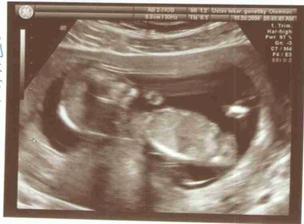

Jsme spolu 15 let,8 let už žijeme ve stejné domáctnosti a letos v červnu 28. jsme se vzali a po svatebních radovánkách přesně 30.06. jsem otěhotněla a tak teď už jsem ve 4.měsíci a čekáme co to bude a těšíme se až budeme tři...lépe řečeno až nás bude o jednoho více...máme 3pejsky,kočku a papouška...takže už je nás v domáctnosti habaděj...Tak čekáme chlapečka,bude se jmenovat Richard...a už jen 3 týdny a snad bude bez komplikací mezi námi...za celé těhotenství jsme neměli žádné problémy tak uvidíme jak proběhne porod a to ostatní...